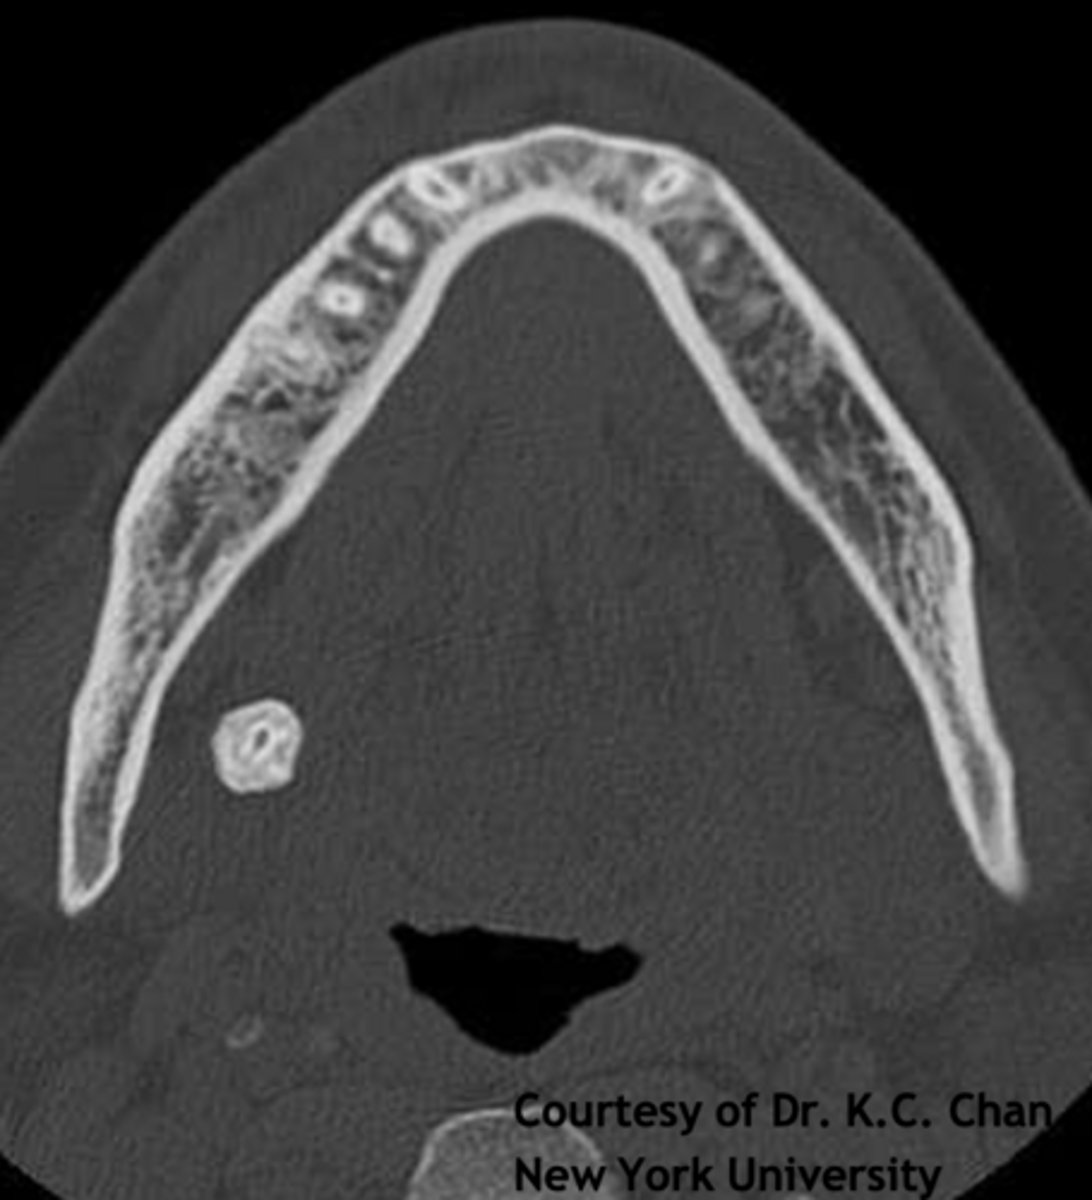

ID the pathology:

Swelling in wharton's duct

Sialolithiasis

ID the pathology during surgery:

Associated with pain upon salivation

What pathology is associated with pain upon salivation?

submandibular gland

80% of Sialolithiasis are associated with what gland?

Radiopaque mass

What is the radiographic features of a

Sialolithiasis?

ID the pathology based on the histology findings:

- Laminated calcified structure with central nidus

- Milking stone toward duct orifice